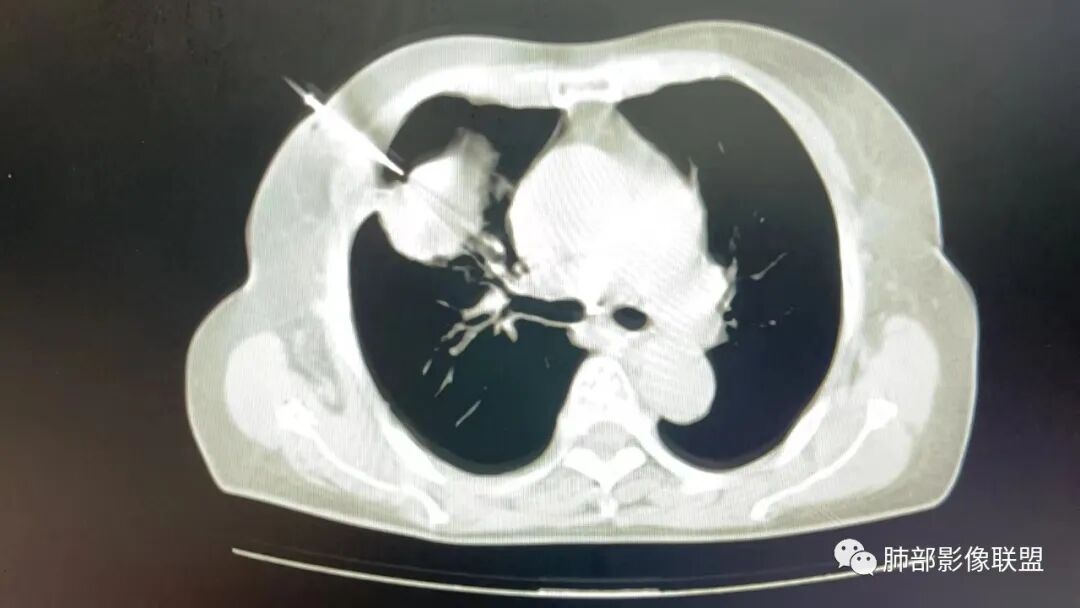

2.影像学特点:右肺上叶前段胸膜下不规则较大团块影,边界清楚欠光整,浅分叶,肺血管支气管出入,边缘膨隆胸膜凹陷具有一定张力,未见典型粗短毛刺,部分围以边界清楚的磨玻璃影,灶周小叶间隔增厚。块影密度不均,渐进性强化,可见砂砾样钙化,未见明显液化坏死或空洞。增强后病灶显示渐进性强化。MIP显示病灶内肺动脉穿行、并部分肺动脉受侵变细。纵隔及右锁骨上(胸廓入口)见肿大淋巴结。两肺可见多发大小不一的结节影,边界清楚,随机分布。

多数学者认为血管支气管包埋征是肺LELC的特征性表现。本组41.97 0A(81/193)病灶内部动脉期见血管包埋征,而血管形态正常,无明显受侵、狭窄,与上述研究报道相符,可能提示肺LELC具有类似淋巴瘤相似的特点,即易浸润周围结构,引起间质增厚、肺泡壁破坏及肺泡腔充盈,但较少侵犯血管[1 3|。但本组108例(108/193,55.96%)表现为血管受侵、狭窄,75.82%支气管受累狭窄闭塞,可能提示肺LELC病灶内血管受侵狭窄及支气管破坏较淋巴瘤更多见[1 3|,较大肺LELC病灶更易出现血管、支气管受侵、破坏。